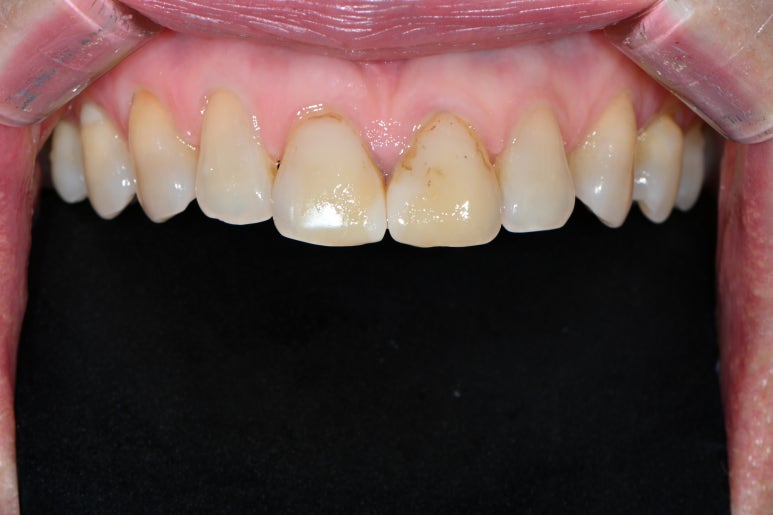

위 치아만 보면 변색이 더욱 도드라집니다. 치아가 얼룩덜룩하죠.?

계속 레진치료만 할 수도 없는 노릇입니다. 변색이 또 생기면 기존 레진 제거하고 더 넓게 떼우고... 또 레진 변색 생기면 더 넓게 떼우고...

혹자는 인스타그램 보면 기가멕히게 레진으로 잘 떼워주시는 분들도 있다고는 하는데, 솔직히 레진 치료 후 몇 년 뒤에 나타날 변색은 치과의사 그 누구도 예상할 수 없으리라 장담합니다.

앞니에 레진치료를 많이 받았던 분들. 과감히 라미네이트를 결정하실만한 이유가 된다고 생각합니다.

오히려 이런 레진 치료보다는 세라믹 재질의 얇~~은 라미네이트를 붙여주는게 훨씬 우월하고 깔끔한 치료니깐요.